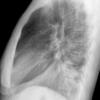

Case 7 RUL pneum Lat

Date: 02/10/2005

Views: 4731